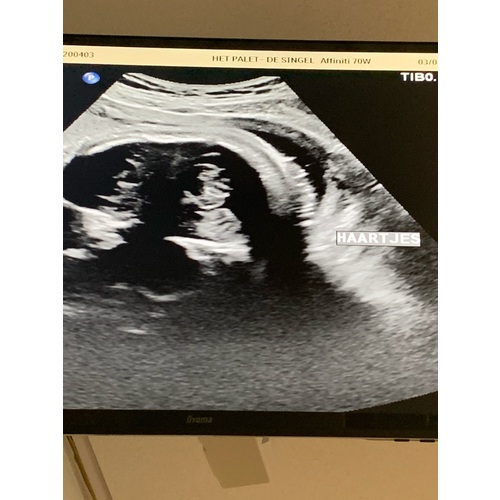

Dit was mijn echo met ‘haartjes’, voor mij abracadabra maar voor de echoscopist heel duidelijk.. onze dochter afgelopen woensdag geboren, lekker veel haartjes (donker) en al echte mooie wenkbrauwen 🥰